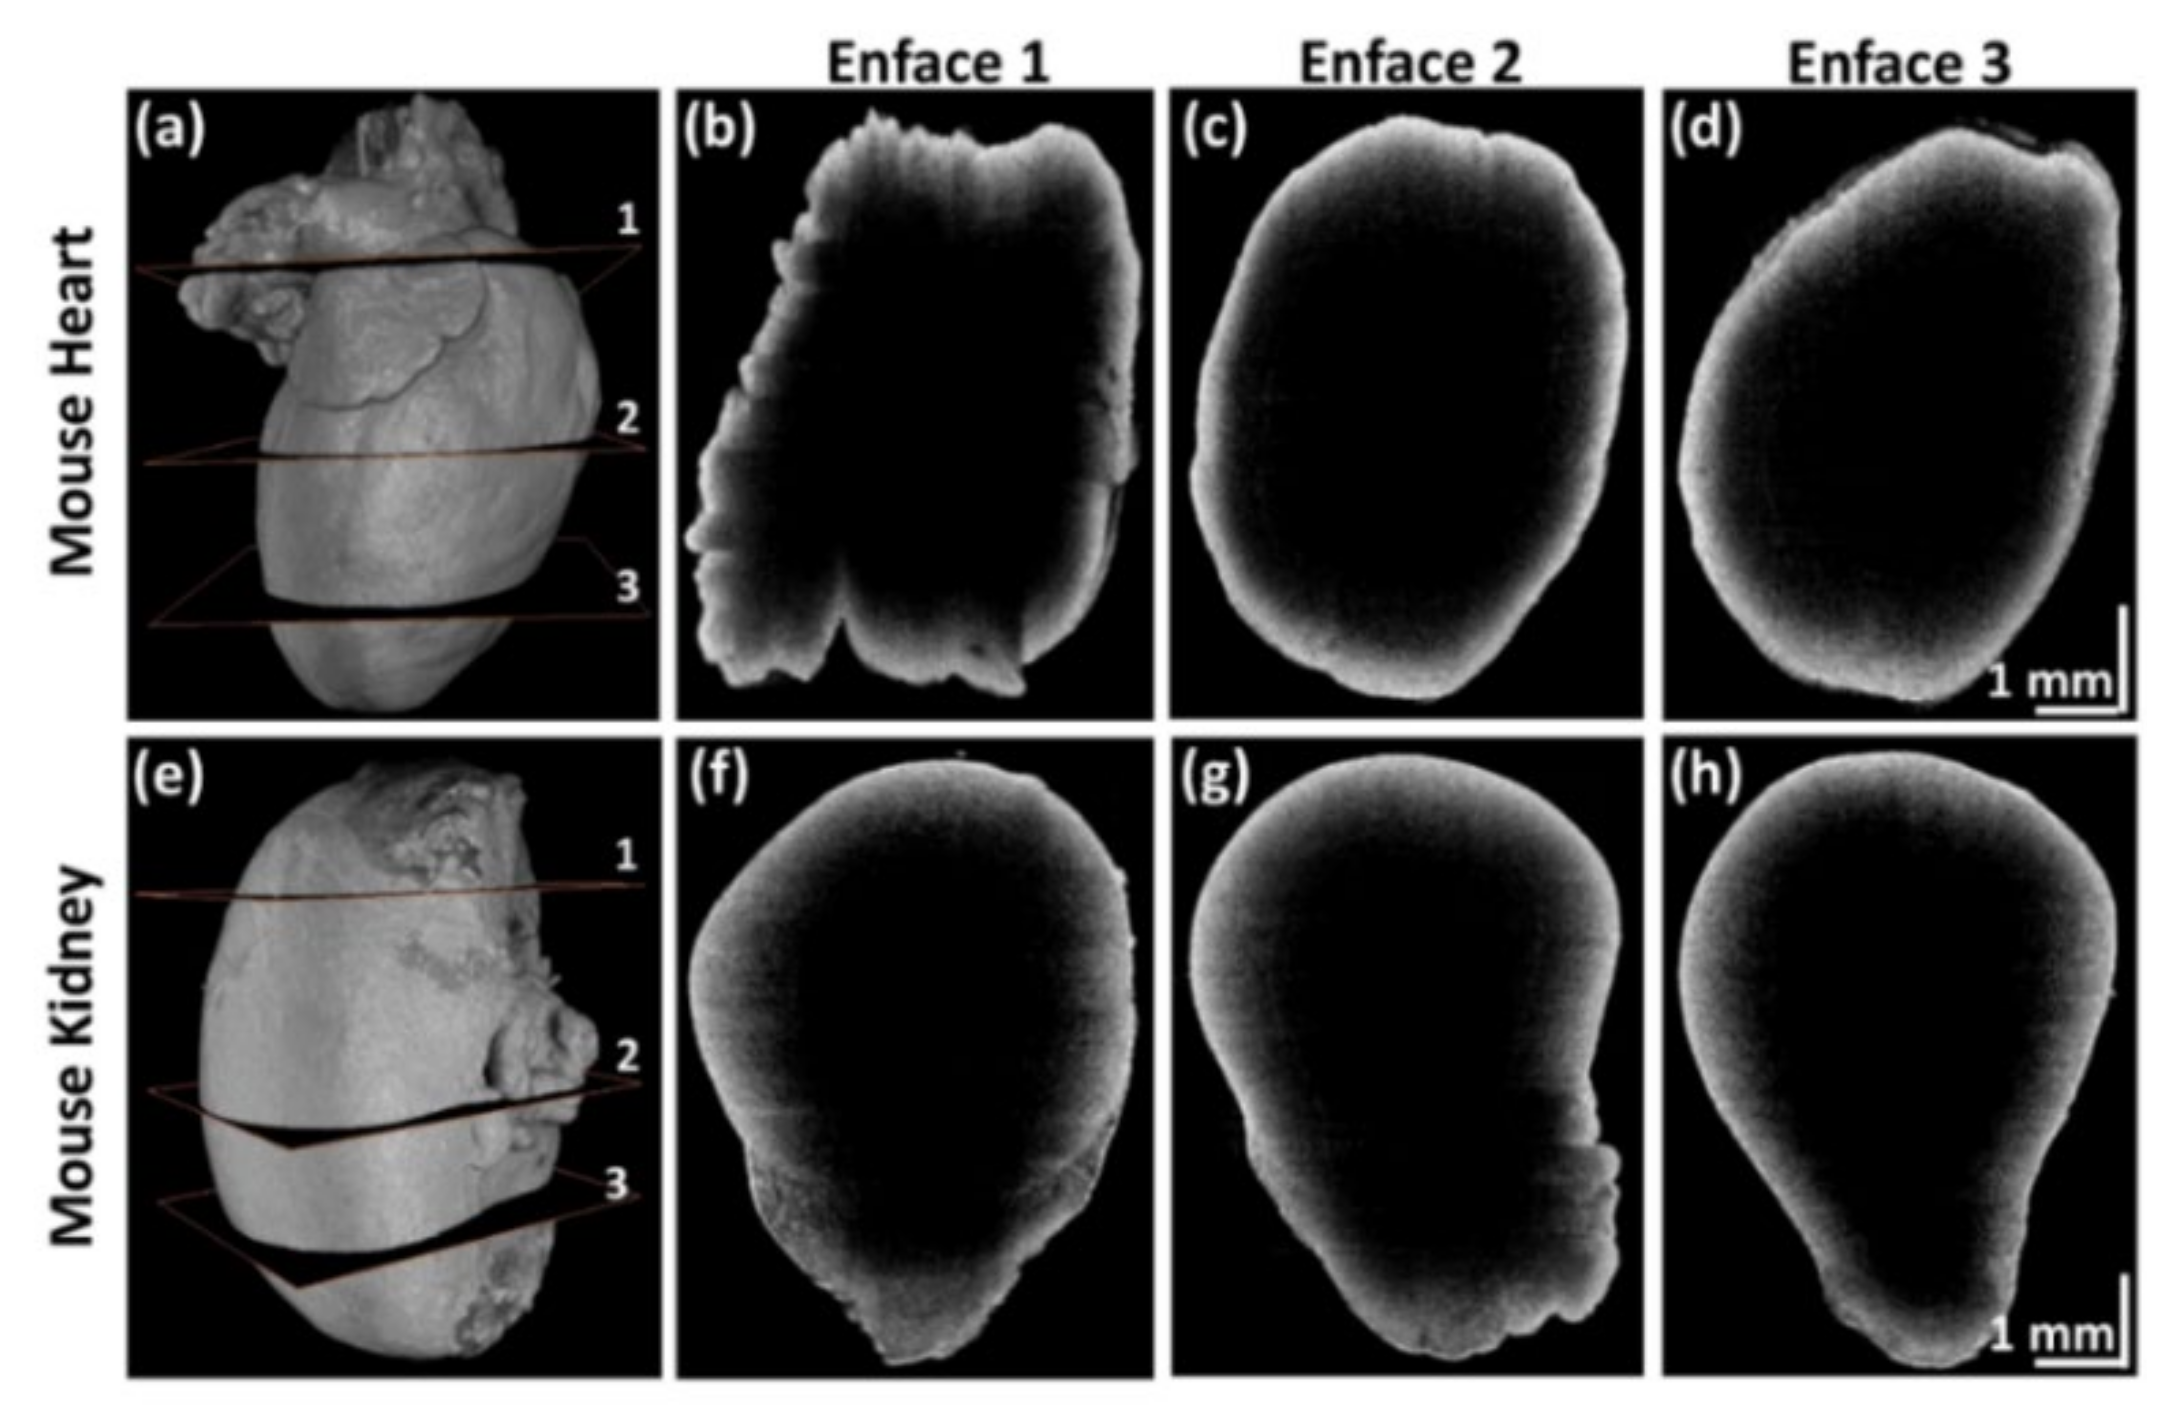

Sequential QS-OCT was developed to overcome the aforementioned limitation of power loss that occurs in the simultaneous QS-OCT system. Sequential QS-OCT utilizes a common reference arm for four different scanners to compensate for the power loss. To verify the performance of sequential QS-OCT in assessing the whole-directional imaging of biological samples, we obtained whole-directional morphological images of a mouse heart and kidney as ex vivo specimens. Following the set value of the A-scan rate (20 kHz), the volumetric imaging of each scanner consumed 36.25 s with 0.0125 μm step sizes of motor movement. Figure 7 shows the cross-sectional OCT images and their merged enface images of mouse heart and kidney specimens. The cross-sectional OCT images shown in Figure 7b–e and Figure 7g–j were obtained using four scanners through whole-directional imaging. These four cross-sectional OCT images were merged using an image processing algorithm, described in Figure 3, to form the enface images shown in Figure 7a,f. All the characteristic features that are seen in the cross-sectional OCT images of the mouse heart and kidney specimens are retained in their respective enface images.

Figure 7.

Enface and cross-sectional OCT images of mouse heart and kidney specimens. (a) and (f) are the enface images of mouse heart and kidney, respectively. (b–e), and (g–j) are the cross-sectional OCT images of mouse heart and kidney, respectively.

Figure 8 shows the 3D volumetric and enface images of mouse heart and kidney specimens acquired in sequential QS-OCT. Full-directional 3D rendering morphological images of the mouse heart and kidney are shown in Figure 8a,e, respectively. Every side of the sample was scanned vertically using a linear motor stage for volumetric imaging (1000 × 2048 × 725 pixels). Independently obtained volumetric images from four different sample arms were merged to obtain enface images with customized rendering software. Figure 8b–d,f–h are the representative enface images that were obtained from three different layers of 3D volumetric imaging of mouse heart and kidney specimens, shown in Figure 8a,e, respectively. The enface images shown in Figure 8b–d,f–h demonstrate the proper merging process for obtaining whole-directional volumetric data of the sample. The obtained 3D volumetric and enface images of the mouse heart and kidney specimens verify the whole-directional imaging capability of QS-OCT.

Figure 8.

3D volumetric and representative enface images of mouse heart and kidney using quad-scanner (QS)-OCT. (a,e) are full-directional 3D rendering morphological images of a mouse heart and kidney; (b–d) and (f–h) are the selected enface images obtained at the three different layers shown in (a,e), respectively.